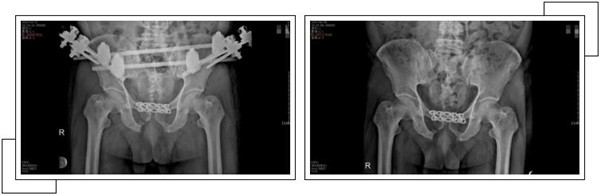

二周后,趙大叔病情穩(wěn)定,身體各方面條件符合手術指征后,骨科中心副主任羅軍帶領手術團隊為其進行了骨盆骨折、恥骨聯(lián)合分離、雙側(cè)髂骨骨折、右側(cè)恥骨上下支骨折切開復位內(nèi)外固定術,手術一個半小時順利完成。

經(jīng)過關節(jié)科全體醫(yī)護人員的精心治療和護理,術后一個月,趙大叔康復出院。出院當天,趙大叔感謝的話說了又說,并在來復查時,特地制作了一面錦旗以表示謝意。